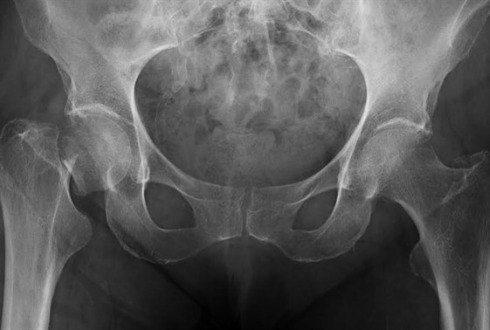

Indicó que el problema de la osteoporosis es que no duele, no hay una sintomatología que avise de la enfermedad, en muchas ocasiones el primer aviso de que alguien tiene osteoporosis es la fractura, que principalmente se da en la muñeca, la columna y la cadera.

"Si tomamos las estadísticas de la Organización Mundial de la Salud, una de cada tres personas arriba de 50 años va a tener osteoporosis en algún momento de su vida, si esta estadística la llevamos a Jalisco, probablemente en el estado haya alrededor de 400 mil personas con osteoporosis en este momento", expuso.

Destacó que de la población de pacientes estudiada durante 2015, 30 por ciento no presentó la enfermedad, 25 por ciento presentó osteopenia (la primera fase de la pérdida de la masa ósea sin llegar a ser osteoporosis) y 45 por ciento de los pacientes, osteoporosis.